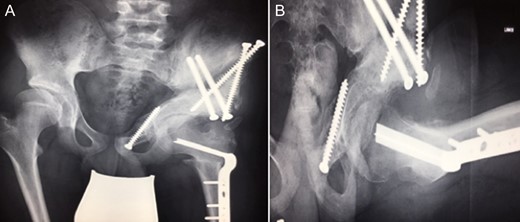

(2008) Despite reconstruction the femoral head subluxated and rapidly lost congruency. An open reduction and capsular reconstruction with trevira tube, removal of the femoral plate and temporary fixation with an external fixator with movable hip mechanism for flexion of the joint (Orthofix MonoRail) was performed.